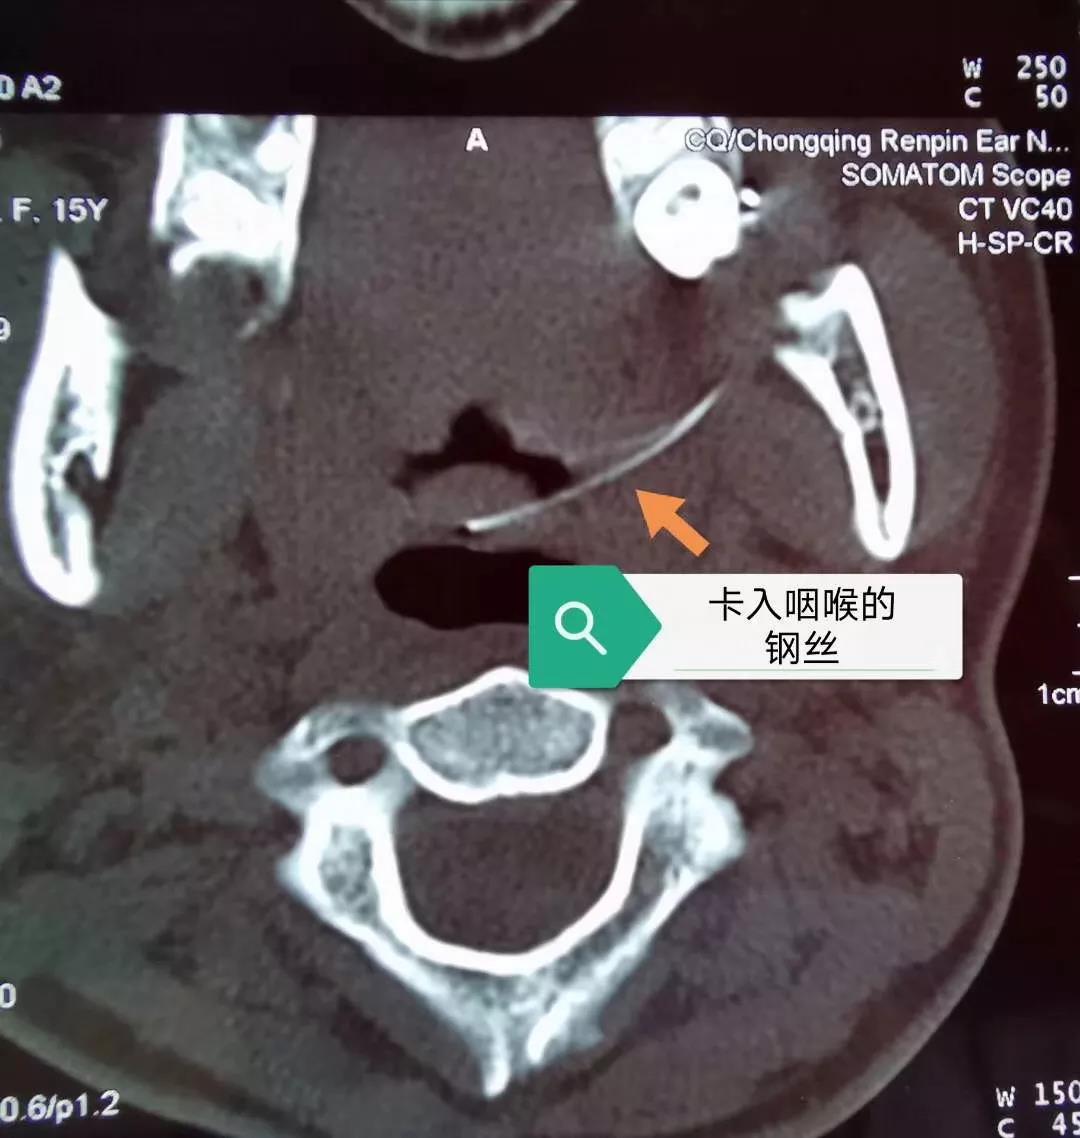

经咽喉部CT提示,一根弯弯的钢丝,牢牢地戳在了患童口咽上腭悬雍垂左侧。

3月28日下午,我院儿童耳鼻喉科马玉龙主任对金金实施了急诊手术,取出了这根困在口腔内20天、长达5厘米的钢丝。因戳入时间过长,有炎症表现,金金粘膜充血,左侧有白色假膜附着,悬雍垂后壁还有少许淋巴滤泡增生。